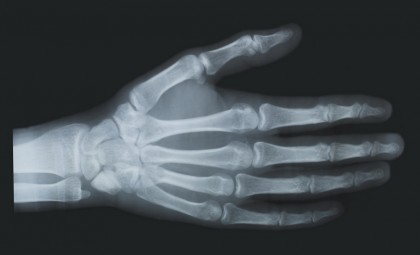

Radiografia reprezintă o imagine bidimensională unică obținută prin generarea și captarea de raze X (raze Röntgen). Tehnica imagistică radiografică are aplicabilitate în multiple domenii, precum medicina dentară, senologie (pentru realizarea mamografiilor), ortopedie, reumatologie, pneumologie și chirurgie (1).

Razele X au capacitatea de a traversa țesuturile organismului uman (epitelial, muscular, conjunctiv, osos). Acestea au grade diferite de radiosensibilitate, astfel că absorb în diferită măsură radiațiile, iar imaginea radiografică (obținută prin proiecția razelor neabsorbite) este o imagine fidelă a dispunerii structurilor și organelor (2).

O radiografie toracică echivalează unei expuneri la 0,1 mSv doză efectivă de radiații, o radiografie dentară la 0,005 mSv, iar o radiografie dentară panoramică la 0,025 mSv, o mamografie în patru planuri însumează aproximativ 0,21 mSv, iar o radiografie de membre și articulații 0,06 mSv (2, 4). Acestea sunt doar valori estimative, iar iradierea reală depinde de mai mulți factori, precum: